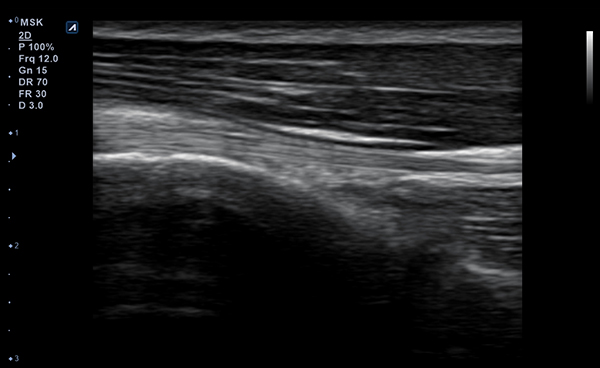

Con Convex y Linear, dos tipos de transductores, puede escanear tanto las

partes más superficiales como las más profundas del cuerpo humano.

Los transductores tienen un amplio rango de aplicaciones y pueden ser utilizados en

una gran variedad de situaciones clínicas.

- Frequency3-12 MHz

- Dimension (height/width/depth)25.2 / 62.5/ 150mm

- Weight 175g

- Field of view 38.4mm

- Max depth10 cm

- Imaging modesB-mode, CF, M, PW, PD

- DisplayMicrosoft Surface

- Battery300 min